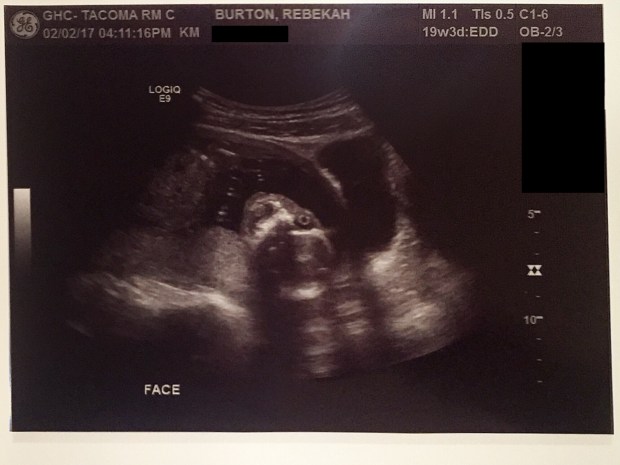

Here’s the most recent pics of Baby Girl!

She stuck her fingers in her mouth

The creepiest picture of all time – Her face looks like a skeleton from Pirates of the Caribbean! I hate this picture.